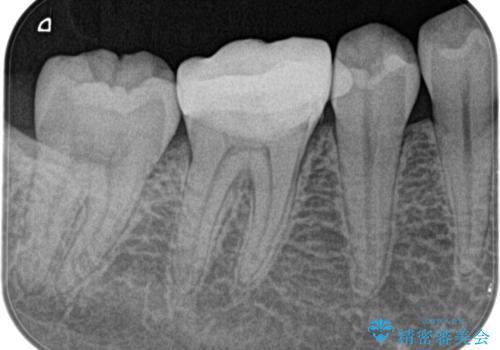

- 奥歯がズキズキ痛いことを主訴に来院されました。

検査の結果、診断を症候性不可逆性歯髄炎、症候性根尖性歯周炎とし抜髄を行っております

根管充填はhydraulic condensation techniqueにて行なっております。

シーラーはWell pulp ST 使用